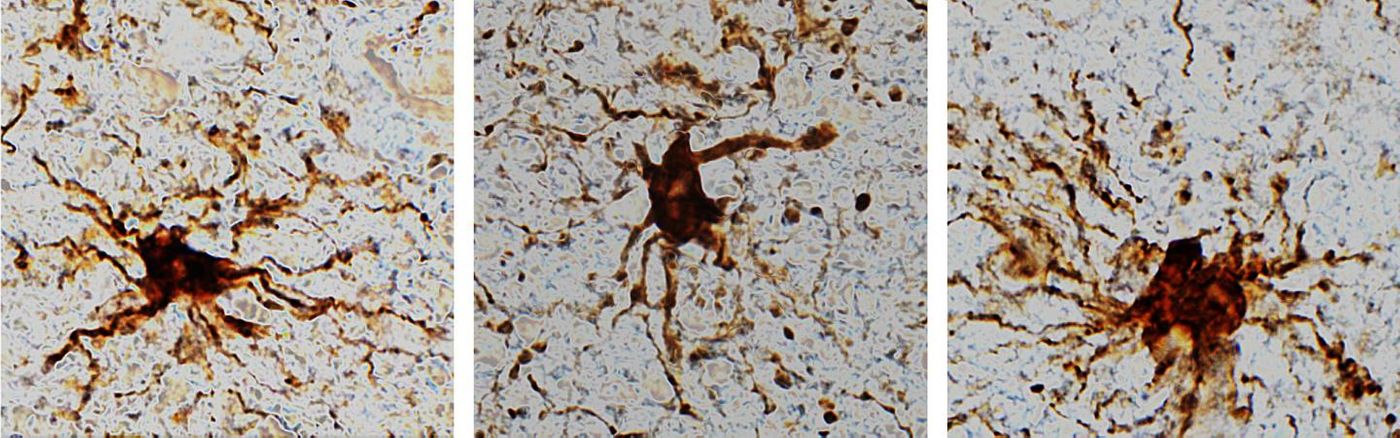

'Zombie' cells come to life after the death of the human brain./Credit: Dr. Jeffrey Loeb/UIC

In this study, the scientists assessed gene expression in brain tissue several times, mimicking the time of death and a post-mortem period. Cells in the brain called glial cells kept expressing genes, and they sprouted large appendages for hours after death.

"That glial cells enlarge after death isn't too surprising given that they are inflammatory and their job is to clean things up after brain injuries like oxygen deprivation or stroke," said corresponding study author Dr. Jeffrey Loeb, the John S. Garvin Professor and head of neurology and rehabilitation at the University of Illinois Chicago College of Medicine.